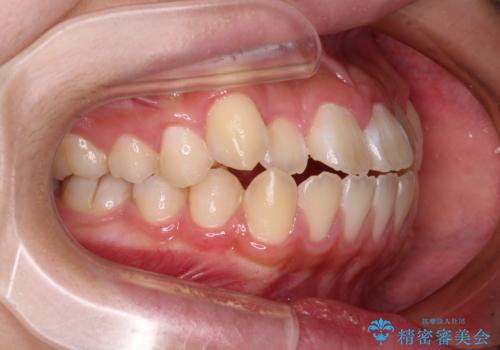

- 前歯が開いて飛び出していることを気にして来院された患者様です。

舌の突出癖により上下前歯は接触できず、更には前方に押し出されて出っ歯になっている状態でした。

上下左右の第一小臼歯4本を抜歯し、ワイヤー装置での抜歯矯正を行っていくのですが、原因である舌の突出癖を改善しないことには治療がうまく進められないため、舌のトレーニングを徹底するよう指導していくこととしました。

当初は舌のトレーニングがうまくできていなかったのですが、途中から奏効し、非常に短い期間で治療を終えることができました。